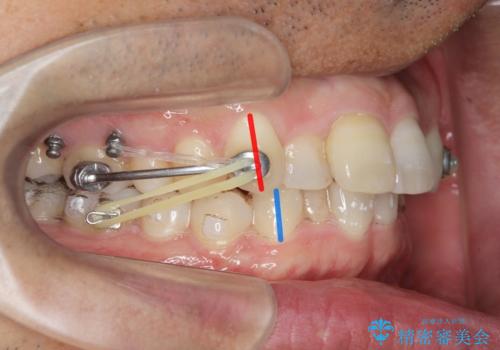

- インビザライン

- 出っ歯に見える前歯を治したい、と矯正治療を希望され来院されました。

奥歯の噛み合わせに大きな問題はないので、目立つ前歯の角度・隙間を重点的に整え、審美的な歯並びを獲得できるよう計画します。